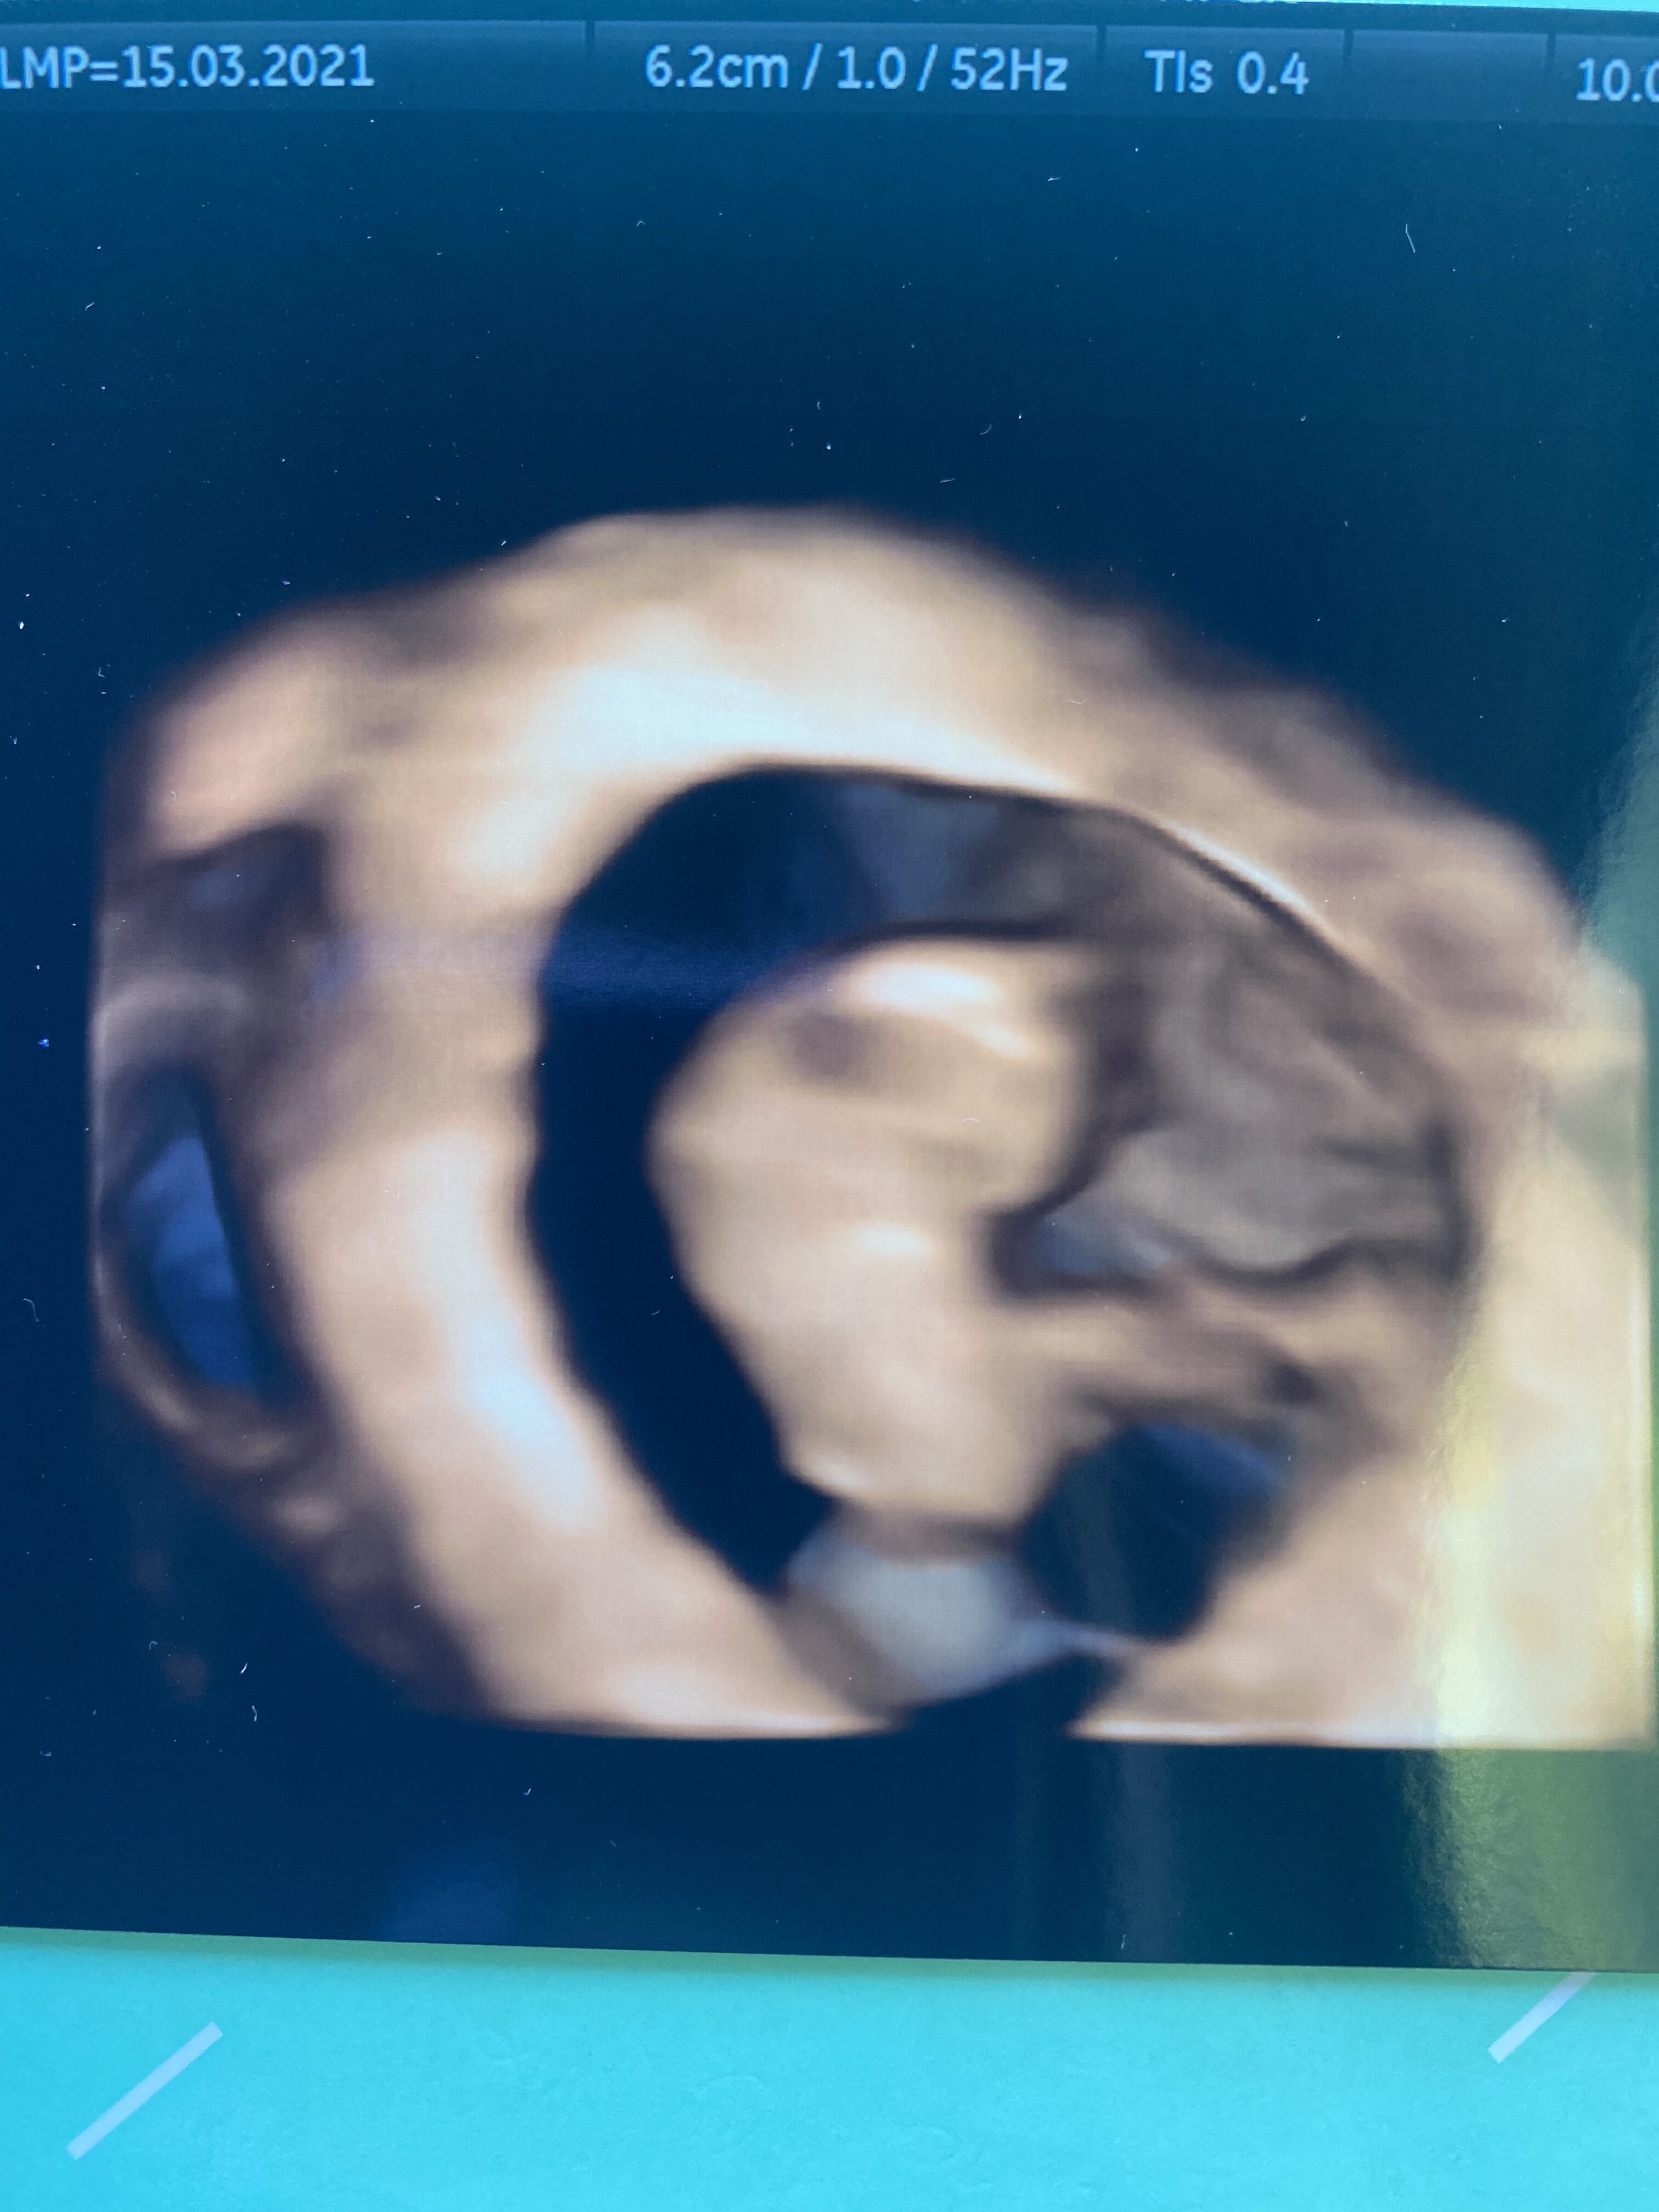

Jestem po wizycie

wszystko jest ok poza tym, ze zrobił się krwiak... termin już drugie usg wychodzi 18.12 i mówi, ze tego mam się trzymać, bo ten będzie wiodący. Wiec wychodzi, ze powinnam zdążyć na Wigilie

taka moja piękna Kruszynka

Słodkie maleństwoJestem po wizyciewszystko jest ok poza tym, ze zrobił się krwiak... termin już drugie usg wychodzi 18.12 i mówi, ze tego mam się trzymać, bo ten będzie wiodący. Wiec wychodzi, ze powinnam zdążyć na Wigilie